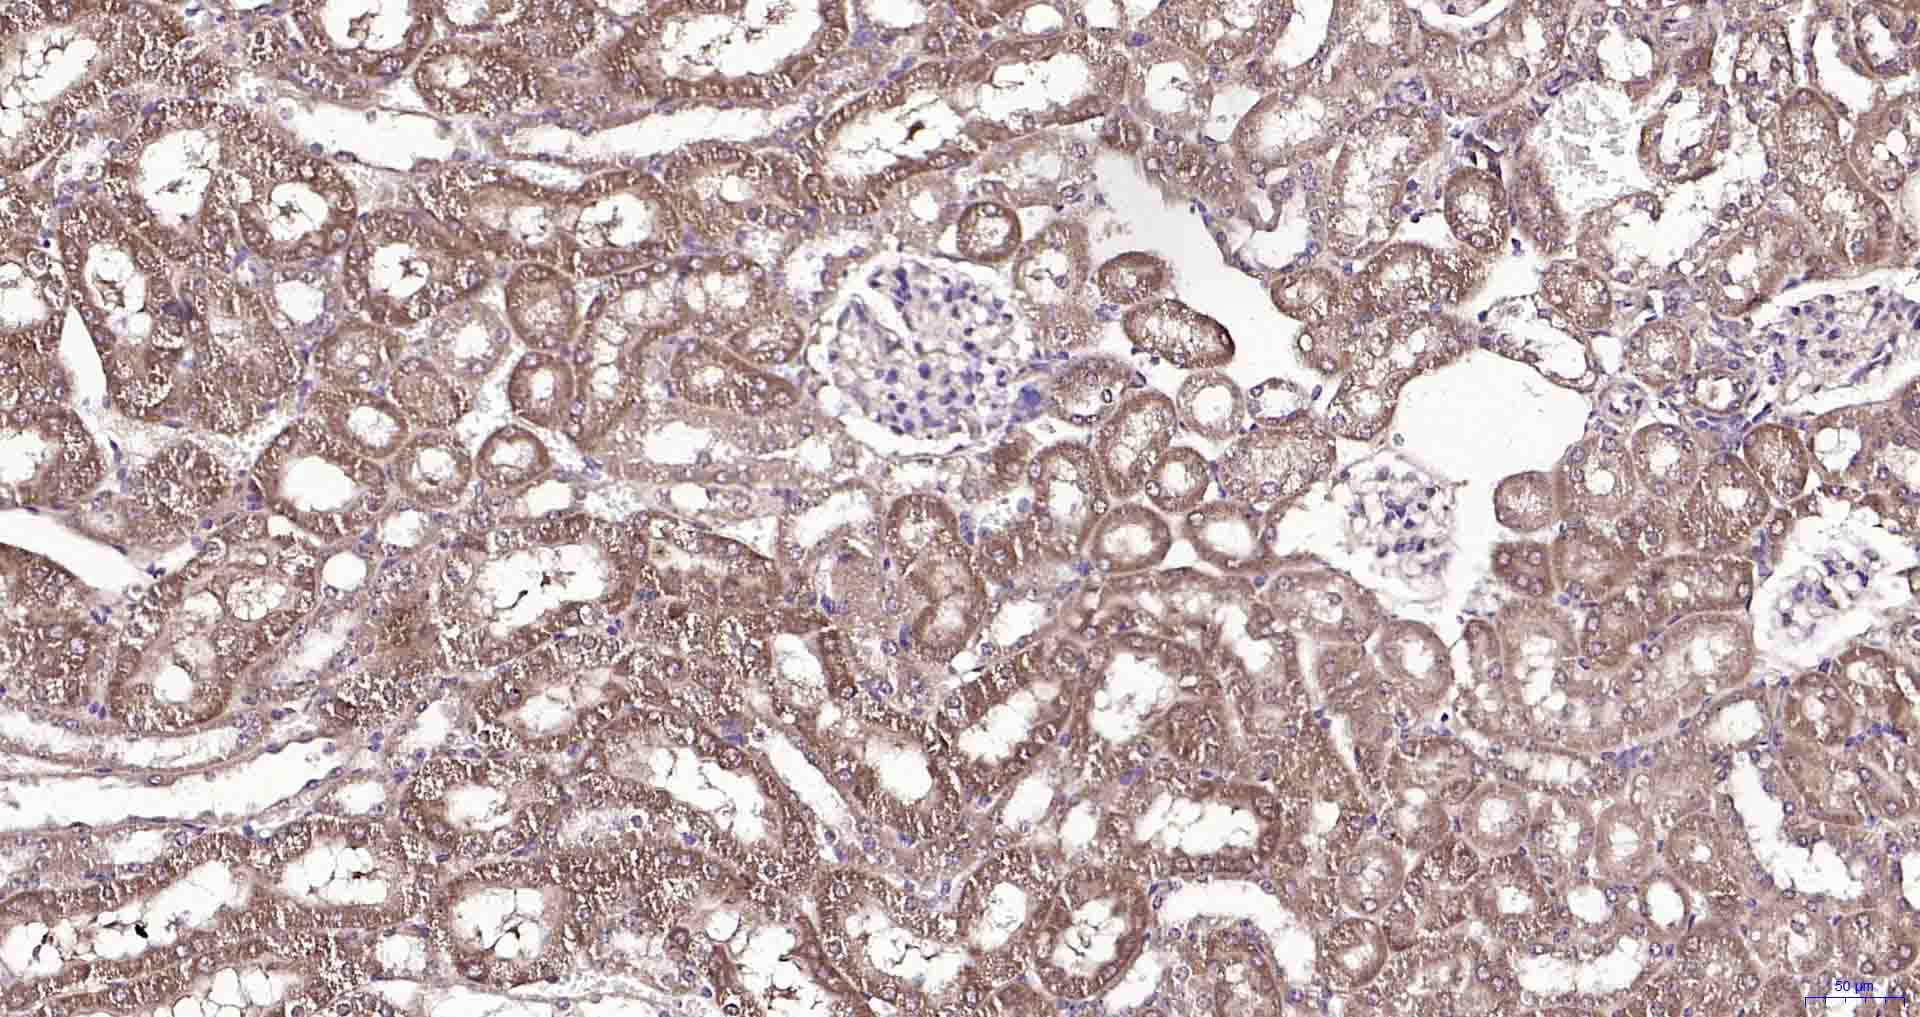

Paraformaldehyde-fixed, paraffin embedded Mouse Kidney; Antigen retrieval by boiling in sodium citrate buffer (pH6.0) for 15 min; Antibody incubation with RILPL2 Polyclonal Antibody, Unconjugated (bs-11944R) at 1:200 overnight at 4°C, followed by conjugation to the SP Kit (Rabbit, SP-0023) and DAB (C-0010) staining.

Paraformaldehyde-fixed, paraffin embedded Rat Kidney; Antigen retrieval by boiling in sodium citrate buffer (pH6.0) for 15 min; Antibody incubation with RILPL2 Polyclonal Antibody, Unconjugated (bs-11944R) at 1:200 overnight at 4°C, followed by conjugation to the SP Kit (Rabbit, SP-0023) and DAB (C-0010) staining.